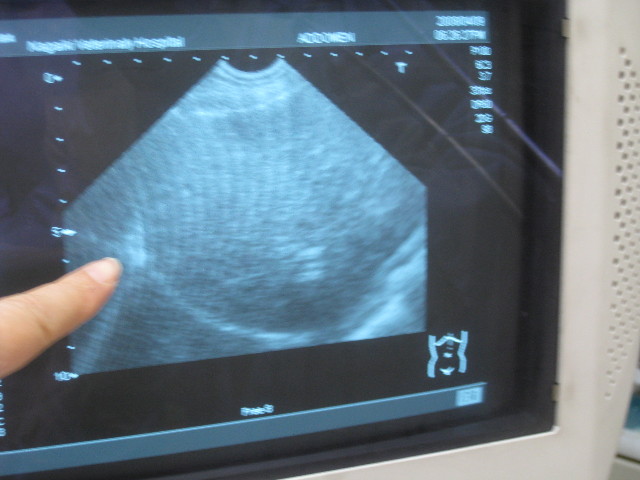

で、問題の肝臓。

肝臓も(腫れていて?)すごくでかいらしい。

でも組織は均一で腫瘍性のものは認められない(^o^)v

指の先は「へんえん(漢字がわからない辺縁かな?)」といって、肝臓の端っこだって。